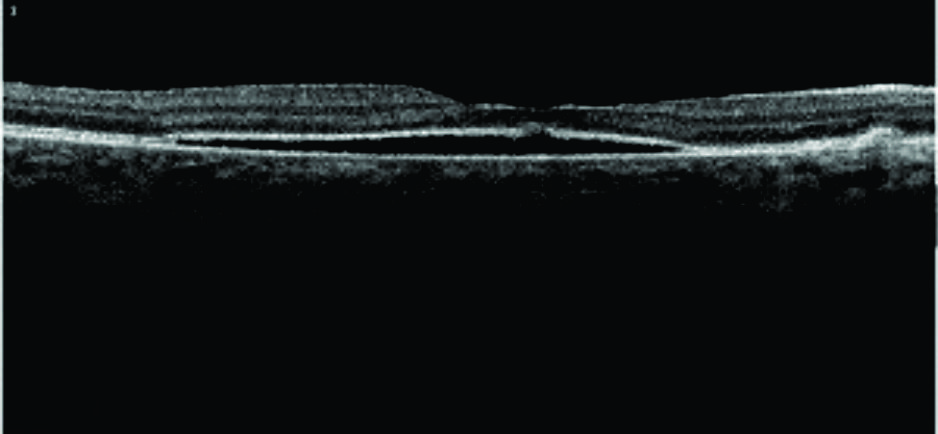

Optic disc pit is a congenital anomaly of the optic nerve frequently associated with macula detachment. It has a poor visual prognosis if left untreated. The treatment of the optic disc remains controversial and includes the use of laser along the edge of the optic nerve, vitrectomy with gas tamponade with or without removal of posterior hyaloid. We report a case of a 19-year-old female with a longstanding macula detachment due to optic disc pit who was treated with vitrectomy with removal of posterior hyaloid, gas tamponade, and laser. Despite longstanding macular detachment the final visual acuity was 20/25.